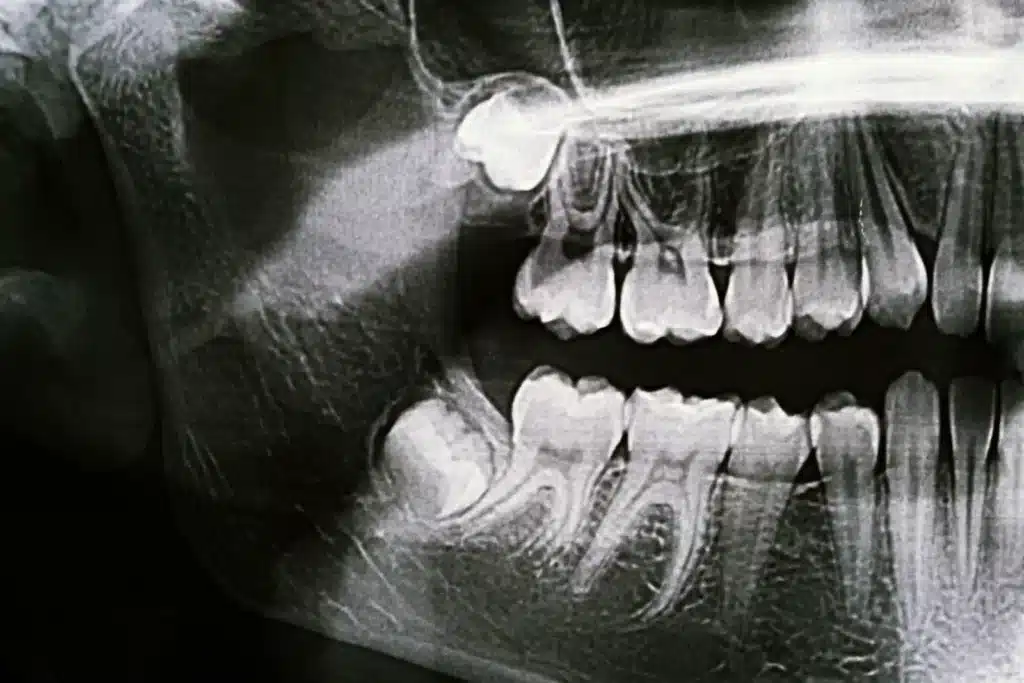

When there is not enough room in the jaw for wisdom teeth to come through properly, they can become trapped under the gum or only partially erupt. Treatment by a qualified dental professional can prevent damage to the neighbouring teeth and supporting bone. Impacted wisdom teeth are common because there is often not enough space in the jaw for them to emerge correctly.

Because of these problems, many oral surgeons and dentists in Brisbane recommend removing troublesome third molars to help keep the gums, jawbone and teeth healthy in the long term.